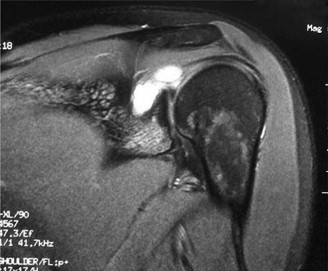

Electrodiagnostic studies (electromyography and nerve conduction velocity studies) are paramount for objective confirmation of SSNE, providing information on nerve demyelination, axonal degeneration, and the level of entrapment. Findings such as increased distal motor latency, decreased nerve conduction velocity across the notch, and denervation potentials (fibrillations, positive sharp waves) or chronic neurogenic changes (polyphasic motor units) in the supraspinatus and/or infraspinatus muscles are highly suggestive. Magnetic resonance imaging (MRI) and magnetic resonance neurography (MRN) are crucial for visualizing the nerve, identifying space-occupying lesions (e.g., ganglion cysts, labral tears), evaluating muscle edema (acute denervation) or fatty atrophy (chronic denervation), and assessing the integrity of the ligaments. Diagnostic injection of local anesthetic into the suprascapular notch can also provide temporary relief and aid in diagnosis.

- Advanced Imaging (MRI/MRN): Detailed review of imaging to identify any space-occupying lesions (ganglion cysts, labral tears, tumors), hypertrophic ligaments, or bony spurs. MRN is particularly useful for visualizing the nerve's course and potential points of compression. The relationship of a cyst to the glenohumeral joint capsule and labrum must be fully understood if a cyst is present.

- Magnetic Resonance Imaging (MRI) / Magnetic Resonance Neurography (MRN): Critical for identifying the anatomical cause of compression. Studies by Donovan et al. and Fritz et al. underscore the utility of MRN in visualizing the nerve path, identifying space-occupying lesions (ganglion cysts, paralabral cysts), and assessing muscle changes (edema in acute denervation, fatty atrophy in chronic denervation). Posterior labral tears are frequently implicated as the origin of spinoglenoid cysts (Snyder et al., Fealy et al.).